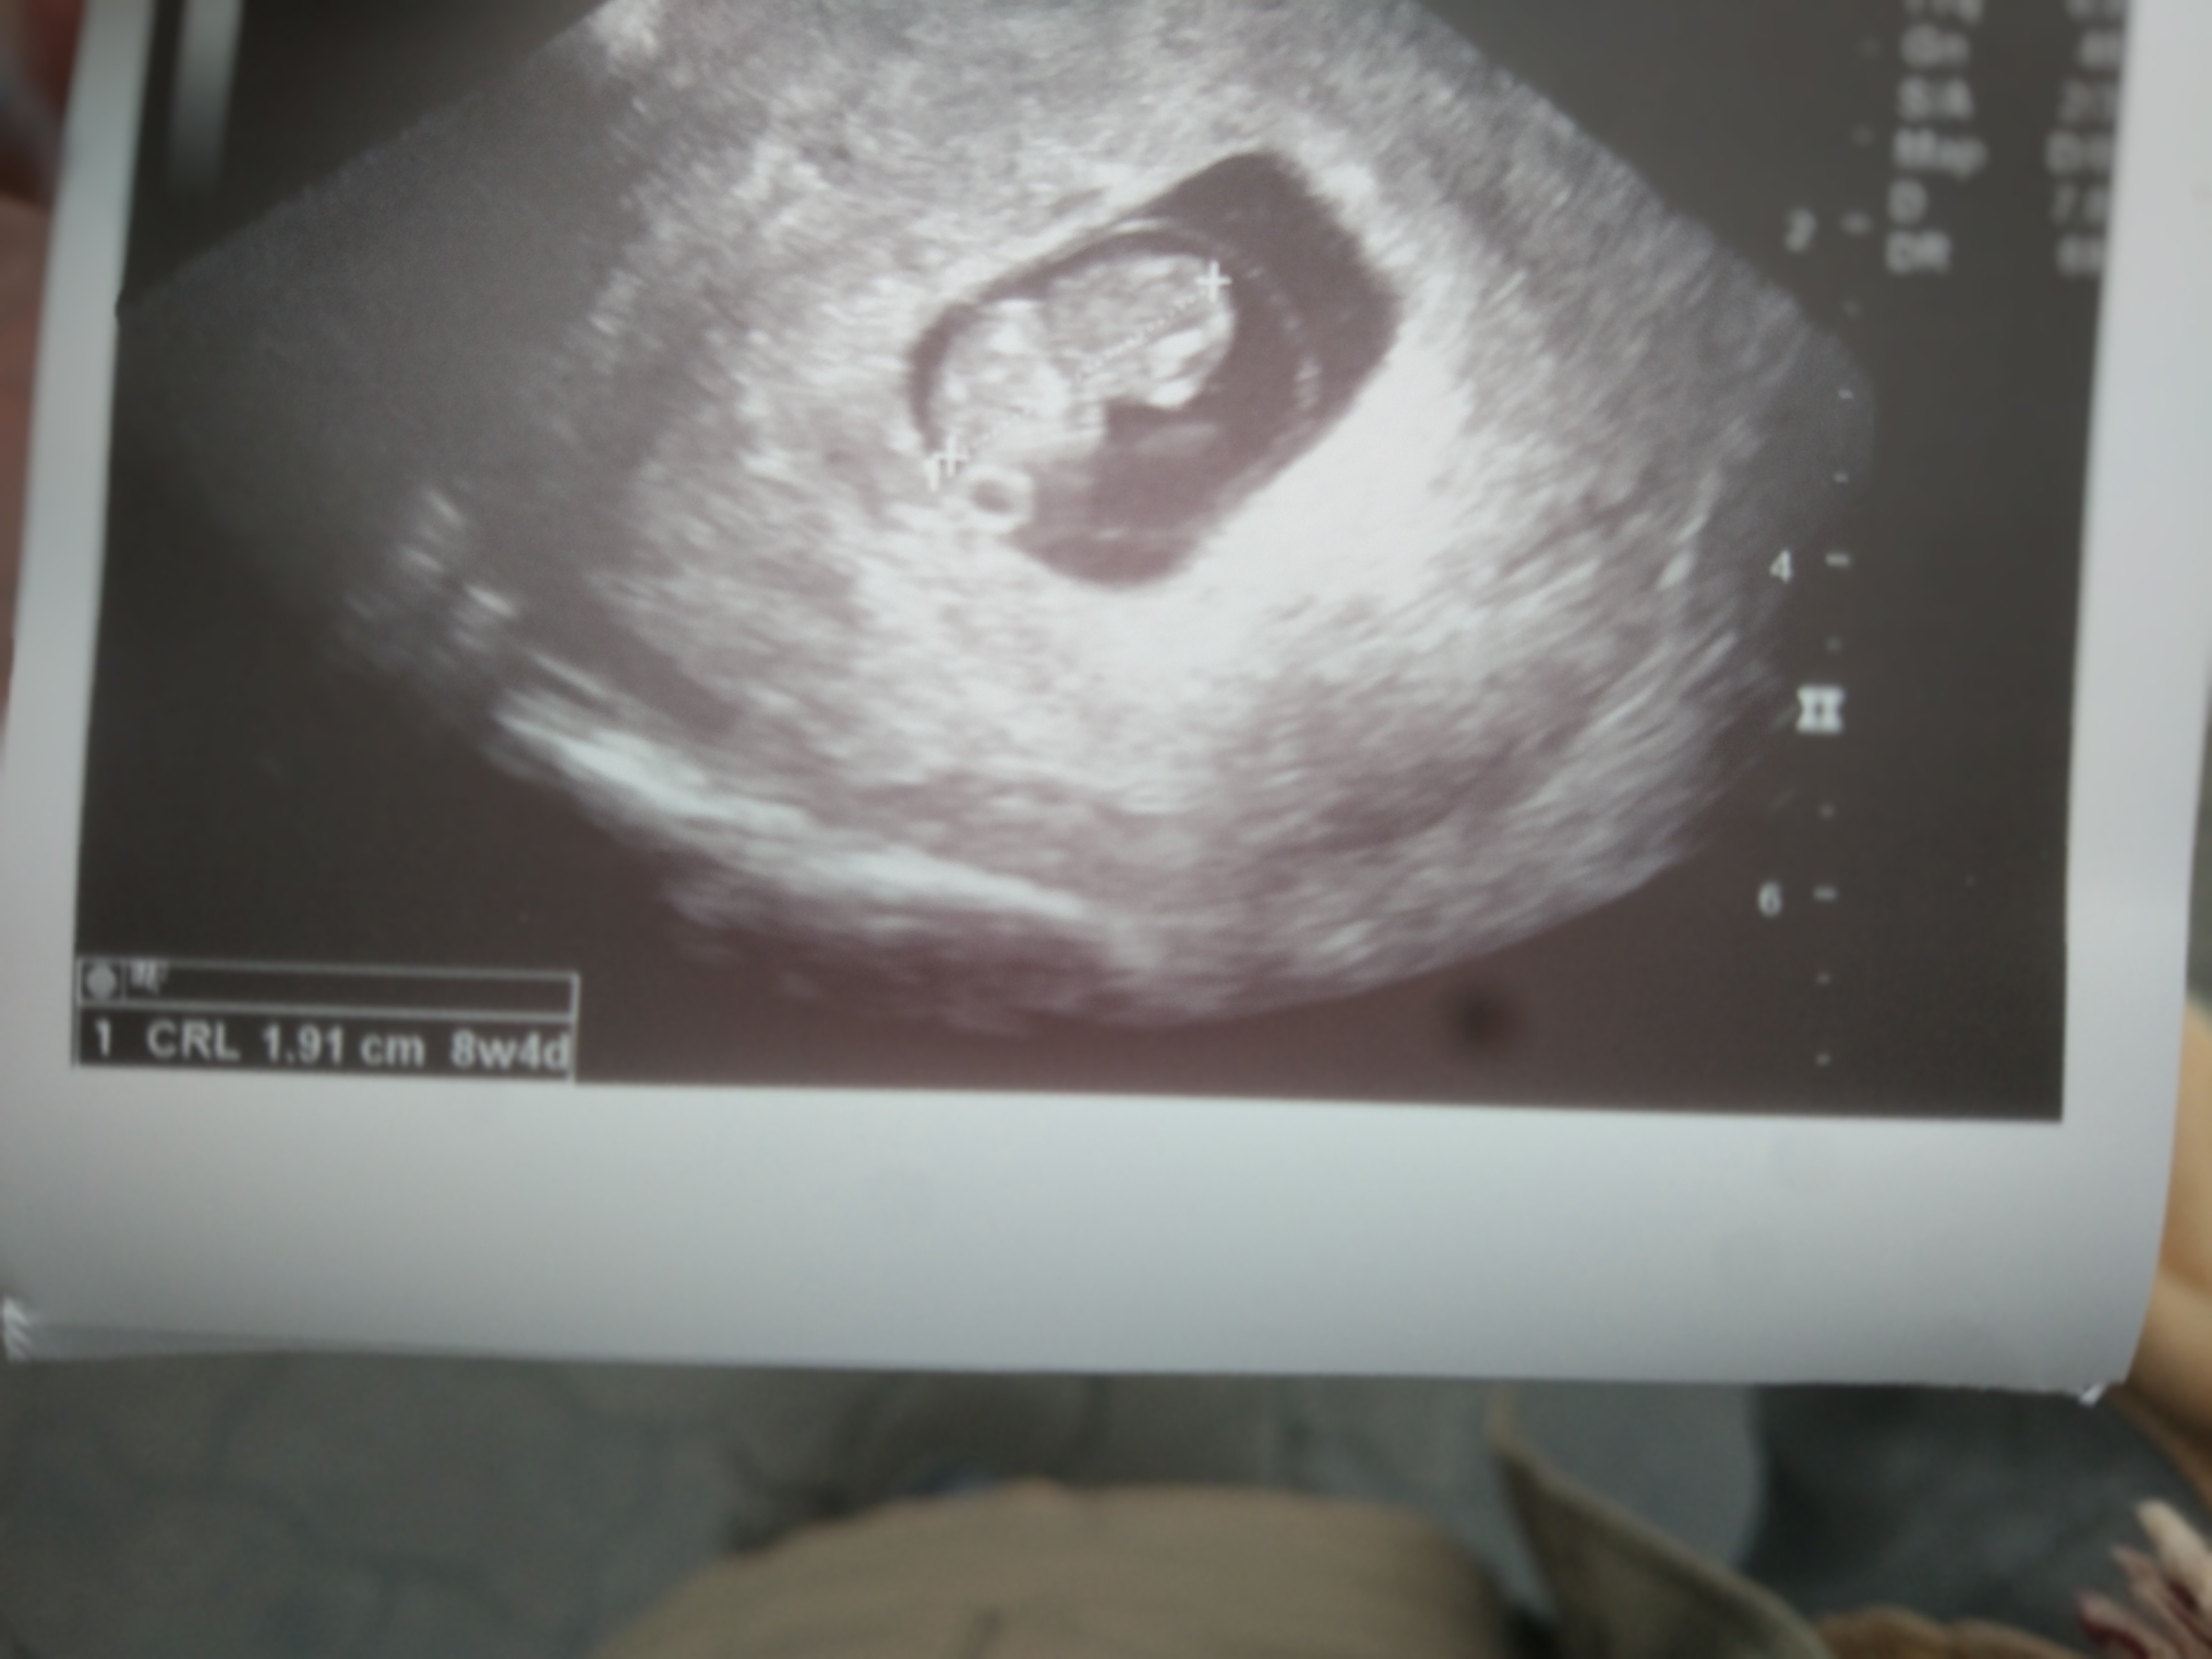

Wszystko dobrze, dzidziuś pięknie rośnie i bije mu serduszko 😍😍💪

• IMG_20200302_111623.jpg

IMG_20200302_111623.jpg

855 KB · Wyświetleń: 126